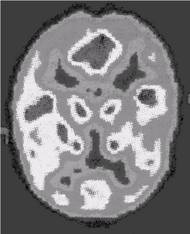

Рис. 3.7. При помощи позитронной эмиссионной трансаксиальной томограммы

(ПЭТТ—сканирование) можно выявить

активацию отдельных участков коры головного

мозга при поступлении и анализе

различной информации

(активация коры и эмоциональных зон мозга, когда испытуемый слушает рассказ о Шерлоке Холмсе)